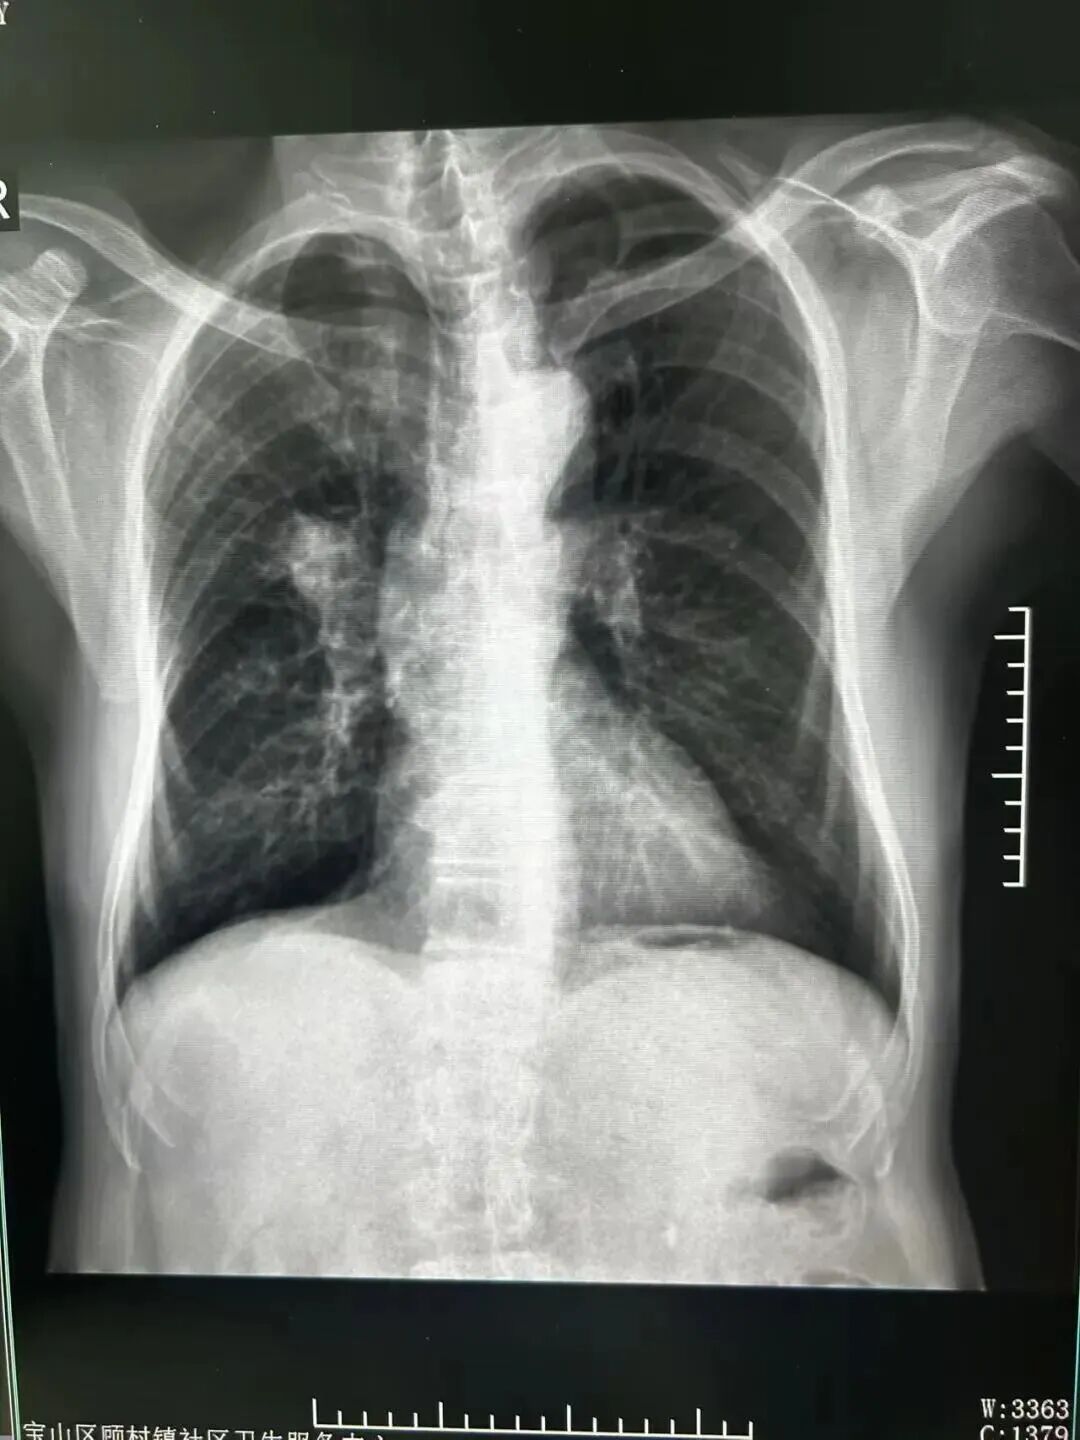

胸片

很快,胸片结果正式出具,提示陈先生肺门处存在占位性病变。中心第一时间为其开通转诊绿色通道,目前陈先生已前往上级医院接受进一步检查治疗。